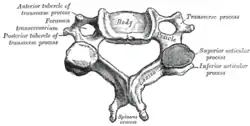

The basic configuration of a vertebra varies, but the bone is its body, with the central part of the body constituting the centrum. The upper (closer to) and lower (further from), respectively, the cranium and its central nervous system surfaces of the vertebra body support attachment to the intervertebral discs. The posterior part of a vertebra forms a vertebral arch (in eleven parts, consisting of

The laminae give attachment to the ligamenta flava, which are ligaments of the spine. There are vertebral notches, each constituted by the shape of the pedicles, which form the intervertebral foramina when [1] vertebrae articulate. These foramina are the entry and exit conduits accommodating the spinal nerves. The body of the vertebra, and it's vertebral arch, form the vertebral foramen, which is the larger, stable and central opening: this accommodates the spinal canal, and encloses and protects the spinal cord.

Every vertebra has a body (vertebral body), which consists of a large anterior middle portion called the centrum (vertebral centrum, plural centra) and a posterior vertebral arch,[3] also called a neural arch.[4] The body is composed of cancellous bone, which is the spongy type of osseous tissue, whose microanatomy has been specifically studied within the pedicle bones.[5] This cancellous bone is in turn, covered by a thin coating of cortical bone (or compact bone), the hard and dense type of osseous tissue. The vertebral arch and processes have thicker coverings of cortical bone. The upper and lower surfaces of the body of the vertebra are flattened and rough in order to give attachment to the intervertebral discs. These surfaces are the vertebral endplates which are in direct contact with the intervertebral discs and form the joint. The endplates are formed from a thickened layer of the cancellous bone of the vertebral body, the top layer being more dense. The endplates function to contain the adjacent discs, to evenly spread the applied loads, and to provide anchorage for the collagen fibers of the disc. They also act as a semi-permeable interface for the exchange of water and solutes.[6]

The vertebral arch is formed by pedicles and laminae. Two pedicles extend from the sides of the vertebral body to join the body to the arch. The pedicles are short thick processes that extend, one from each side, posteriorly, from the junctions of the posteriolateral surfaces of the centrum, on its upper surface. From each pedicle a broad plate, a lamina, projects backwards and medialwards to join and complete the vertebral arch and form the posterior border of the vertebral foramen, which completes the triangle of the vertebral foramen.[7] The upper surfaces of the laminae are rough to give attachment to the ligamenta flava. These ligaments connect the laminae of adjacent vertebra along the length of the spine from the level of the second cervical vertebra. Above and below the pedicles are shallow depressions called vertebral notches (superior and inferior). When the vertebrae articulate the notches align with those on adjacent vertebrae and these form the openings of the intervertebral foramina. The foramina allow the entry and exit of the spinal nerves from each vertebra, together with associated blood vessels. The articulating vertebrae provide a strong pillar of support for the body.

Processes

There are seven processes projecting from the vertebra:

- one spinous process

- two transverse processes

- four articular processes

A major part of a vertebra is a backward extending spinous process (sometimes called the neural spine) which projects centrally.[8] This process points dorsally and caudally from the junction of the laminae.[8] The spinous process serves to attach muscles and ligaments.

The two transverse processes, one on each side of the vertebral body, project laterally from either side at the point where the lamina joins the pedicle, between the superior and inferior articular processes.[8] They also serve for the attachment of muscles and ligaments, in particular the intertransverse ligaments. There is a facet on each of the transverse processes of thoracic vertebrae which articulates with the tubercle of the rib.[9] A facet on each side of the thoracic vertebral body articulates with the head of the rib. The transverse process of a lumbar vertebra is also sometimes called the costal[10][11] or costiform process[12] because it corresponds to a rudimentary rib (costa) which, as opposed to the thorax, is not developed in the lumbar region.[12][13]

There are superior and inferior articular facet joints on each side of the vertebra, which serve to restrict the range of movement possible. These facets are joined by a thin portion of the vertebral arch called the pars interarticularis.